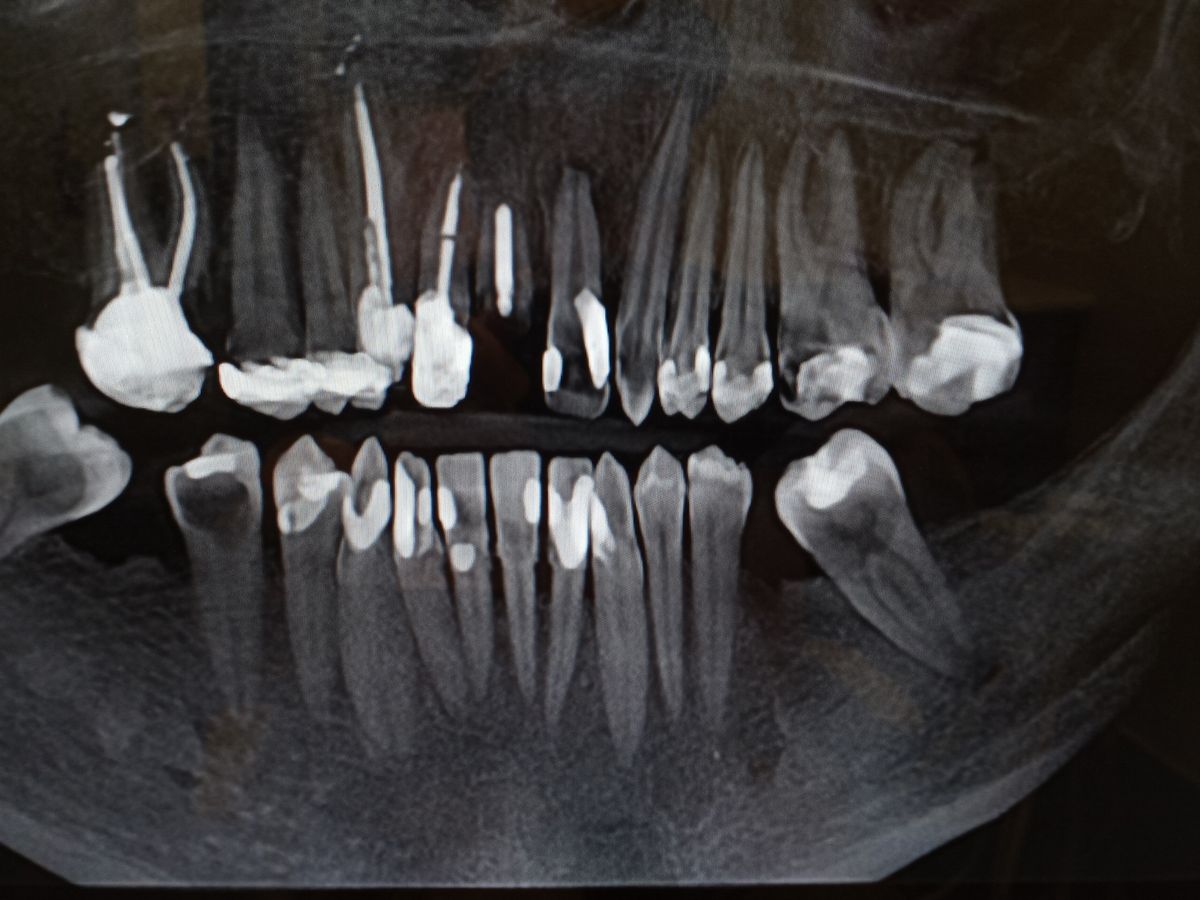

Sadly this insecurity came with a huge price, my life or my hard work and earnings! I was told, seeing that I have put off further work since my last tooth extraction, that I have about 4 to 5 decent enough teeth to work from but cheapest route and suggested from multiple dentist is teeth extractions, bone grafts, implants and then dentures to follow. Cost rises for more secured procedures by the $1,000s! Rough estimate all together could range from $10,000 to $20,000 plus! I can set up plans to pay. Again, not easy for my low income, only provider, household. But now have to factor in the missed work. I've miss almost two weeks now over the absess tooth that has put me into the E.R. on occasion and now waiting for the first tooth extraction and bone grafting on Friday. Then consultation on July 19th the extract all teeth within my mouth. And prior dental work as can be seen on my stories image. When they told me this news I cried! I'm a photographer, a cook, a dad, a lover and a MAN! What will everyone think of me now! Doing art/Horror related alone has been trying around majority of my community. But I still smirk! I still make all around me laugh. Enjoy time spent what ever it is we are doing at that given moment. But inside, especially my mouth, I hurt. I suffer. And I'm so exhausted from this, I can only hope that this story hits someone's heart that could possibly afford a little time or money towards this new path I must take but fear it alone could break us and lose everything I've pushed so hard for.

My story is simple, I have bad teeth and my pride is slowly slipping away as I lose hope in ever truly smiling nor ever being able to afford not only that smile but my health. My heart. Mind. I need some help and have nothing else to lose other than my teeth or life! :(